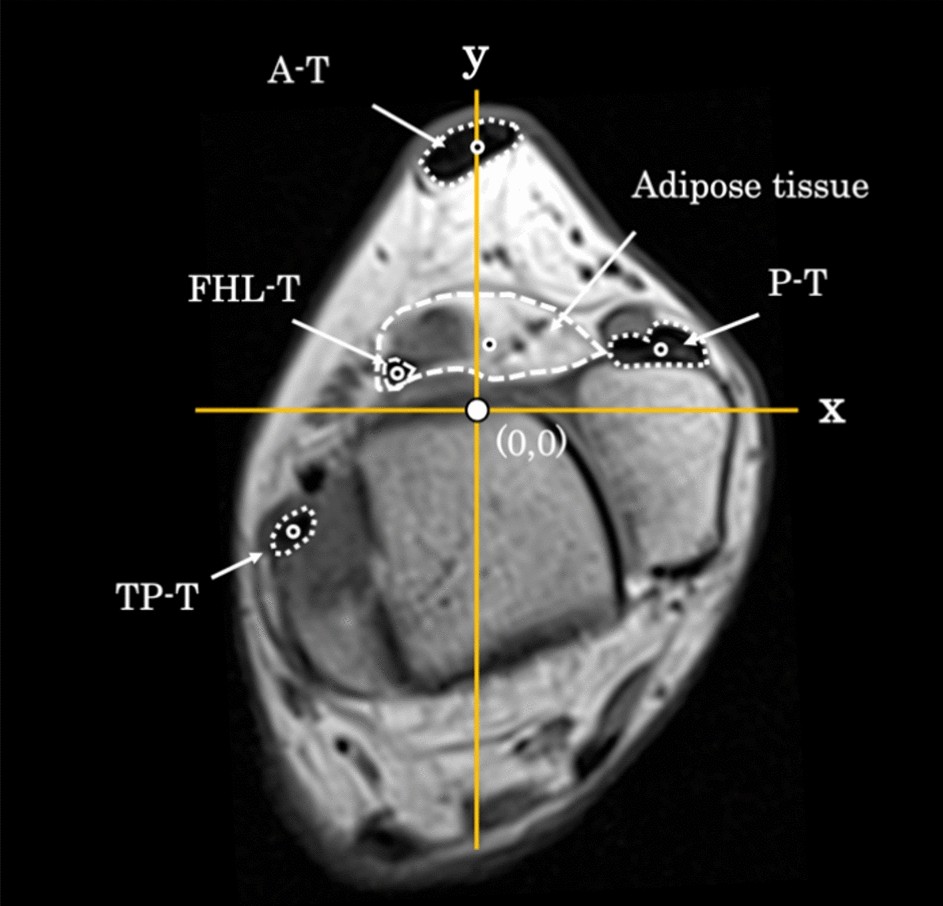

Coordinate center of each tissue. White circle: origin. Black circle: coordinate center of each tissue. FHL-T, flexor hallucis longus tendon; A-T, Achilles tendon; P-T, peroneal tendon, TP-T, tibialis posterior tendon.